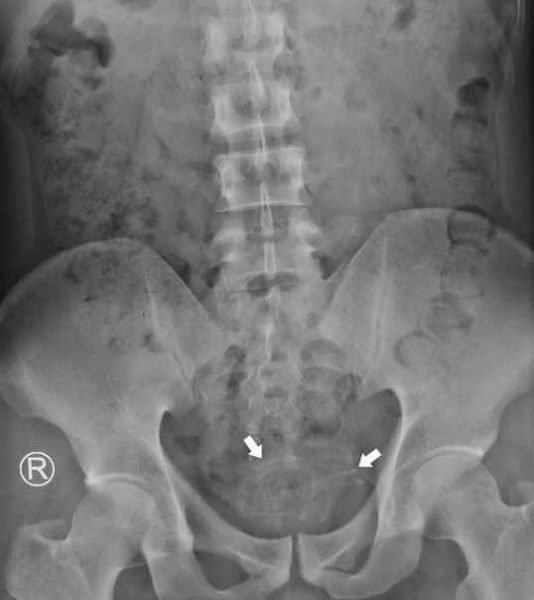

The wire had been coiled and fortunately not attached to the bladder wall, with an extraction carried out using grasping forceps, while the earphone wire was said to be 2-3mm in size and 80cm in length.